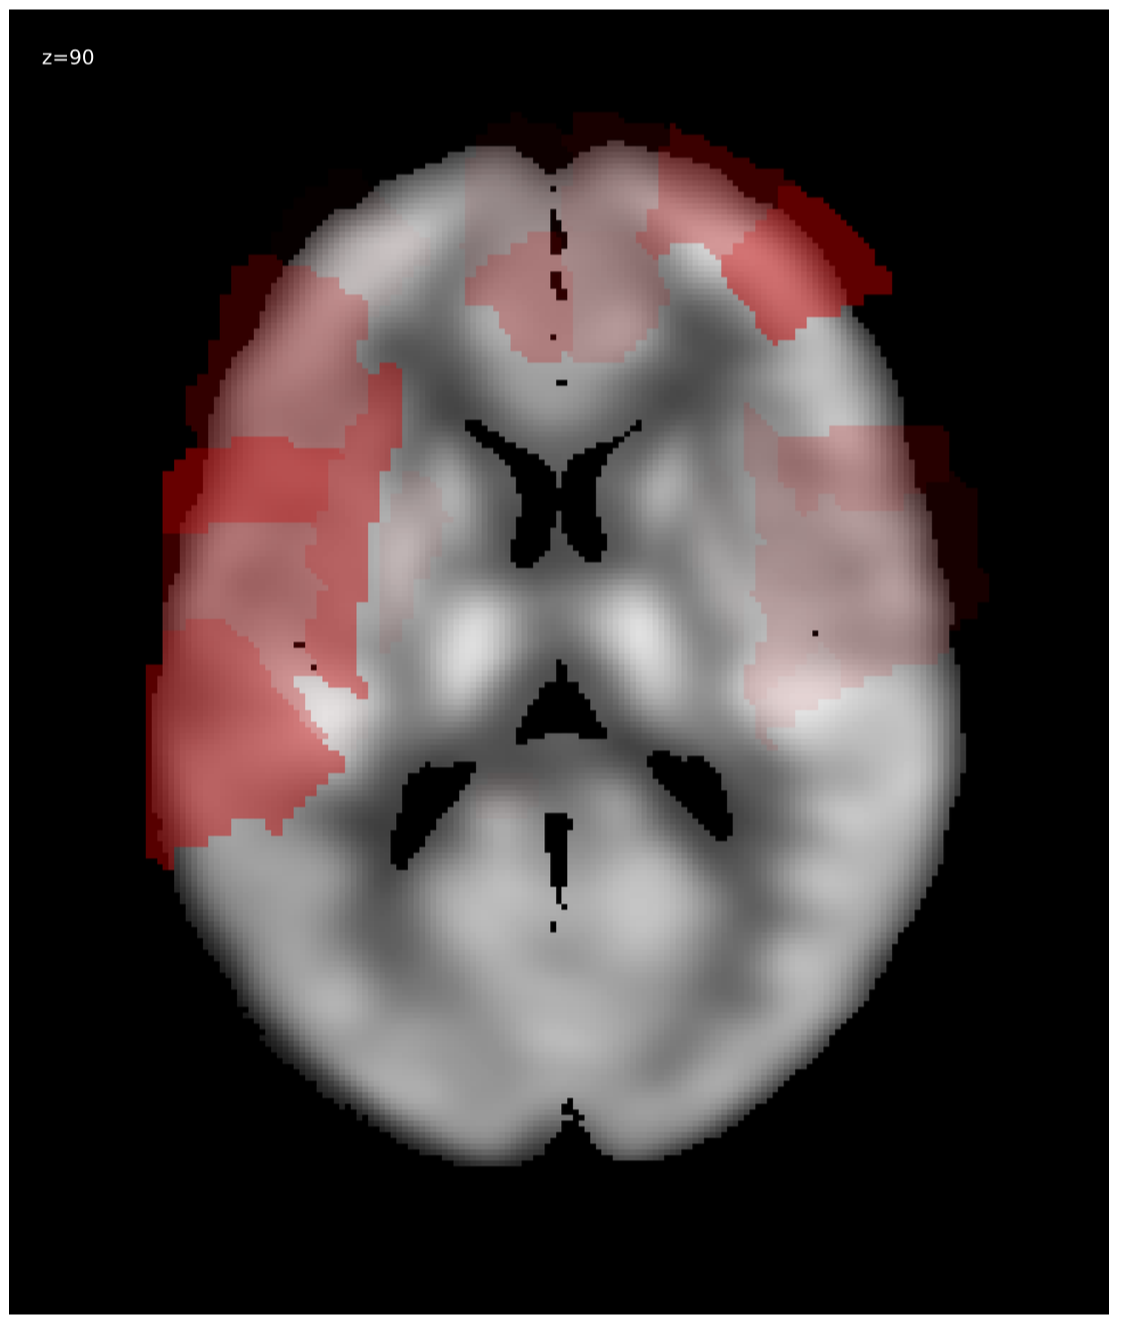

We generated relevance heatmaps for all visualizations methods, averaged over AD PET images in the test dataset. Figure 2 presents the visual comparison of these five methods. The red areas/dots indicate that regions were important for the decision making of the 3D-CNN model. From the result, we can see that all the visualization focuses mostly on similar brain regions. There are some differences, such as the heatmaps generated for the gradient-based methods are distributed. The heatmaps highlight the areas that the CNN network is most susceptible. For the LRP method, the heatmap shows the average relevance of each voxel for contributing to the AD diagnosis score. The heatmaps generated by the occlusion based methods are more focused on the specific regions and cannot administer with large areas of distributed relevance. The reason behind the issue is the occlusion path was not able to cover those areas (for example, the cortex) completely. Brain area occlusion presents very high relevance for the temporal lobe. Since in this method, only one area is covered at a time, that can cause such high importance for one region and minimal relevance for other regions.

To evaluate the visualization result, we consider the literature available from the medical domain [16], [19], as there is no ground truth for validating the generated heatmaps. Table. 1 presents the top five most relevant regions for each visualization method. The relevance in each area following the AAL atlas was summed together to identify the most relevant areas for AD PET scans. From the top five relevant brain areas for each visualization method, we can see that the 3D-CNN focuses on the temporal lobe area, including the hippocampus for CN/AD classification. So, our findings are similar to those in the medical literature [16], [19].